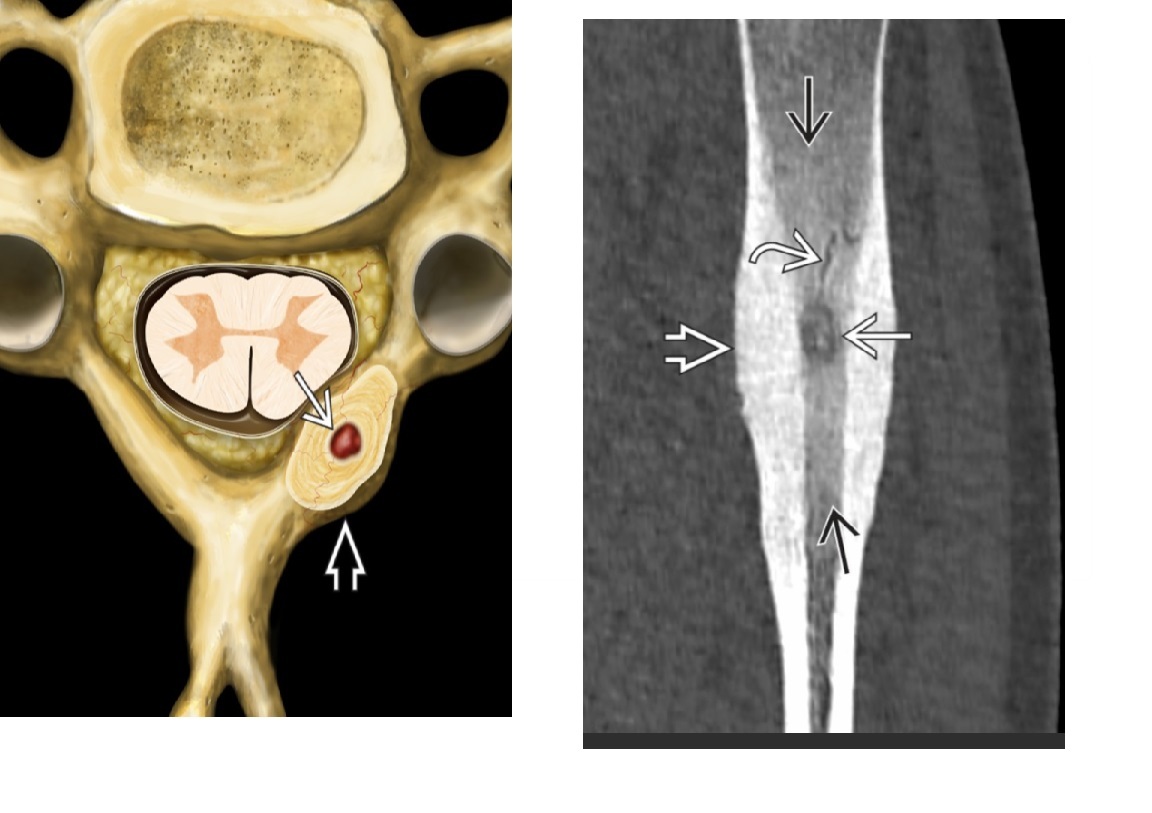

causes of posterior vertebral scalloping?

SATAN Syringomyelia/Dural ectasia Acromegaly Tumours - (ependymoma, lipoma , dermoid, neurofibroma) Achondroplasia NF - 1 also Connective tissue disease - marfans, ehler danlos Mucopolysacchardoses - hurlers, murquio - VERTEBAL BEAKING